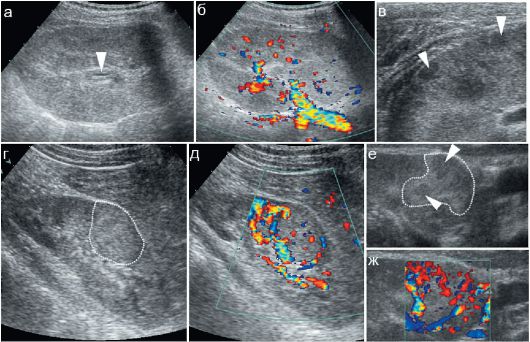

- УЗИ почек при пиелонефрите;